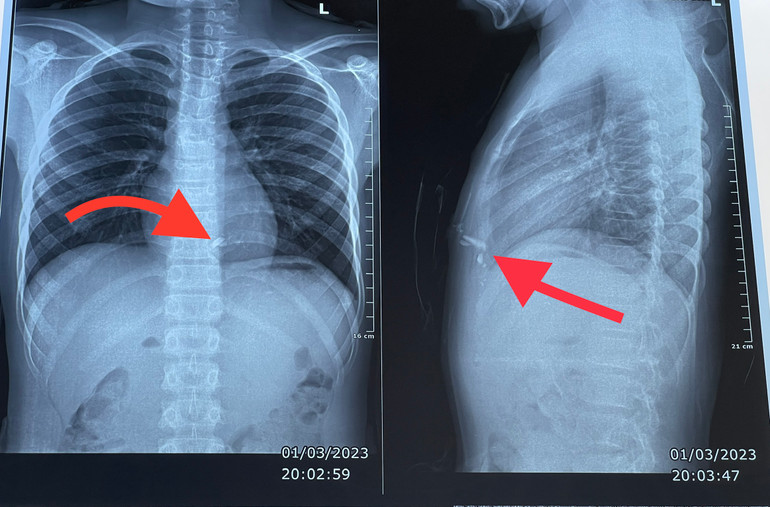

Kết quả chụp phim X-quang ngực thấy có 2 dị vật kim loại trong lồng ngực nằm sau xương ức bên trái, nghi ngờ tổn thương tim. Các bác sĩ đã nhanh chóng mổ cấp cứu kịp thời lấy dị vật, khâu vết thương thành thất phải cho bệnh nhân.

| Hình ảnh 2 dị vật kim loại trong lồng ngực nằm sau xương ức bên trái của bệnh nhân. |